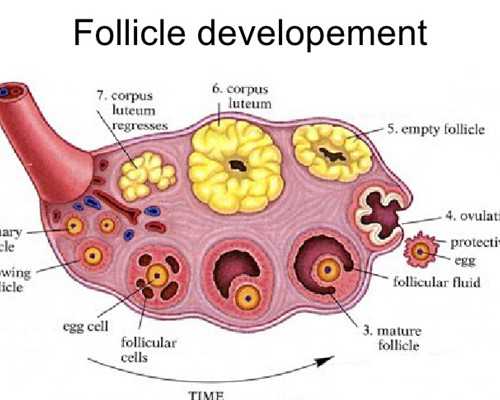

當(dāng)女方來(lái)例假第二天開(kāi)始進(jìn)入試管嬰兒周期,第一步就是促排,通過(guò)藥物給予卵泡一定的營(yíng)養(yǎng),使多個(gè)卵泡能夠同時(shí)發(fā)育成熟,提高受孕率,因?yàn)槊總€(gè)人的卵巢反應(yīng)程度不同,方案和用藥量也不同,所以費(fèi)用會(huì)有一定差異。